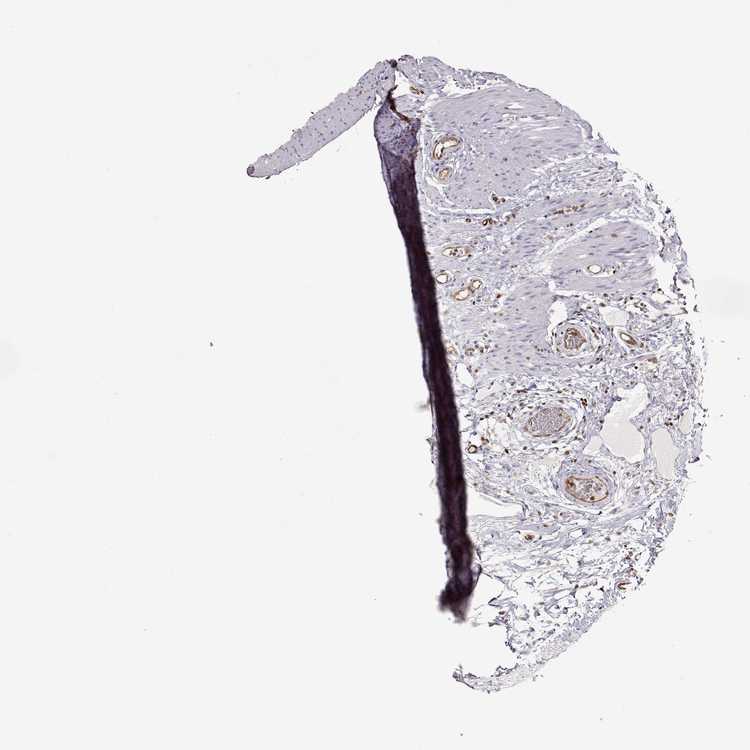

COLON - Antibody stainingi

Antibody staining in the annotated cell types in the current human tissue is reported as not detected, low, medium, or high, based on conventional immunohistochemistry profiling in selected tissues. This score is based on the combination of the staining intensity and fraction of stained cells.

Each image is clickable and will lead to virtual microscopy that enables deeper exploration of all samples and also displays staining intensity scores, fraction scores and subcellular localization as well as patient and tissue information for each sample.

Antibody HPA001625

Endocrine cells Medium

Endothelial cells Not detected

Enterocytes Medium

Enterocytes - Microvilli High

Fibroblasts Not detected

Goblet cells Medium

Mucosal lymphoid cells Not detected